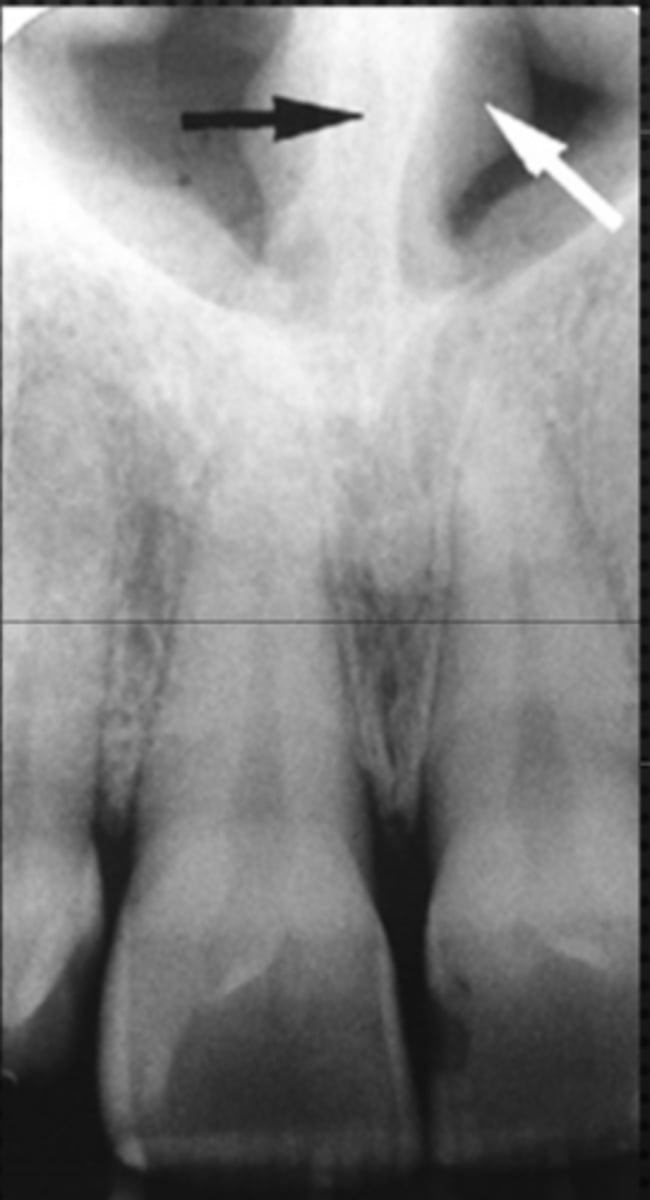

Black arrow - Nasal septum

White arrow- nasal conchae

Identify both structures

<p>Identify both structures</p>

Name the structure the white arrow is pointing to.

<p>Name the structure the white arrow is pointing to.</p>

internal oblique ridge or mylohyoid ridge

Name structure the black arrow is pointing to.

<p>Name structure the black arrow is pointing to.</p>